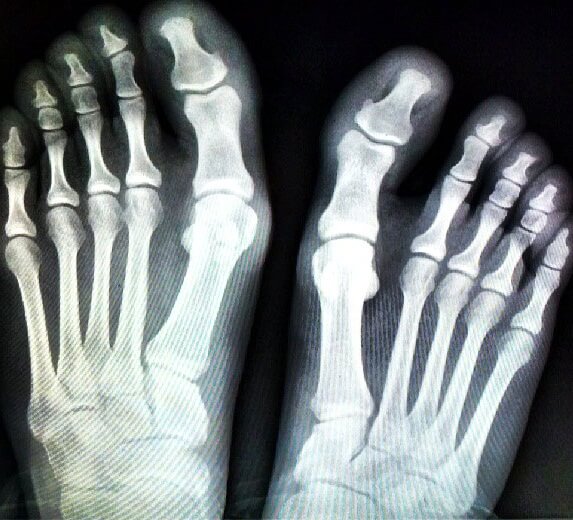

Для постановки точного диагноза могут потребоваться следующие исследования:

- УЗИ сосудов ног;

- рентген нижних конечностей;

- анализ крови.